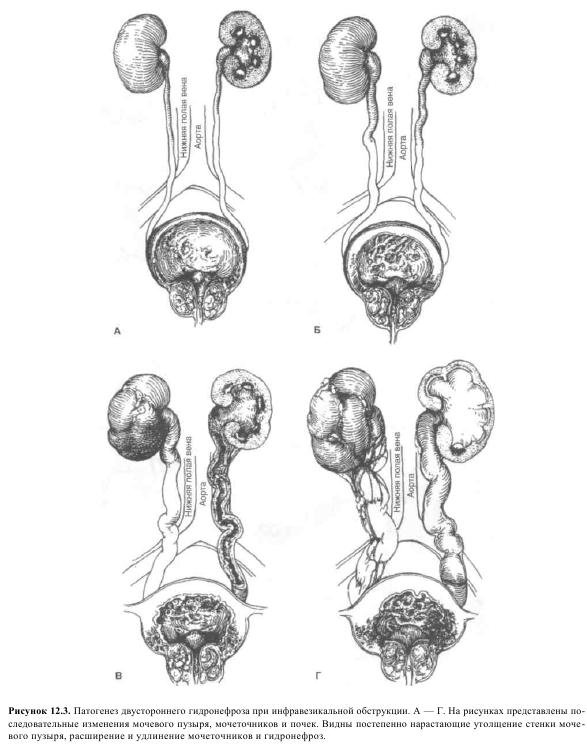

Рефлюксирующий мегауретер: Визуализация и медицинские изображения

Раздел: Фотопуть к знанию